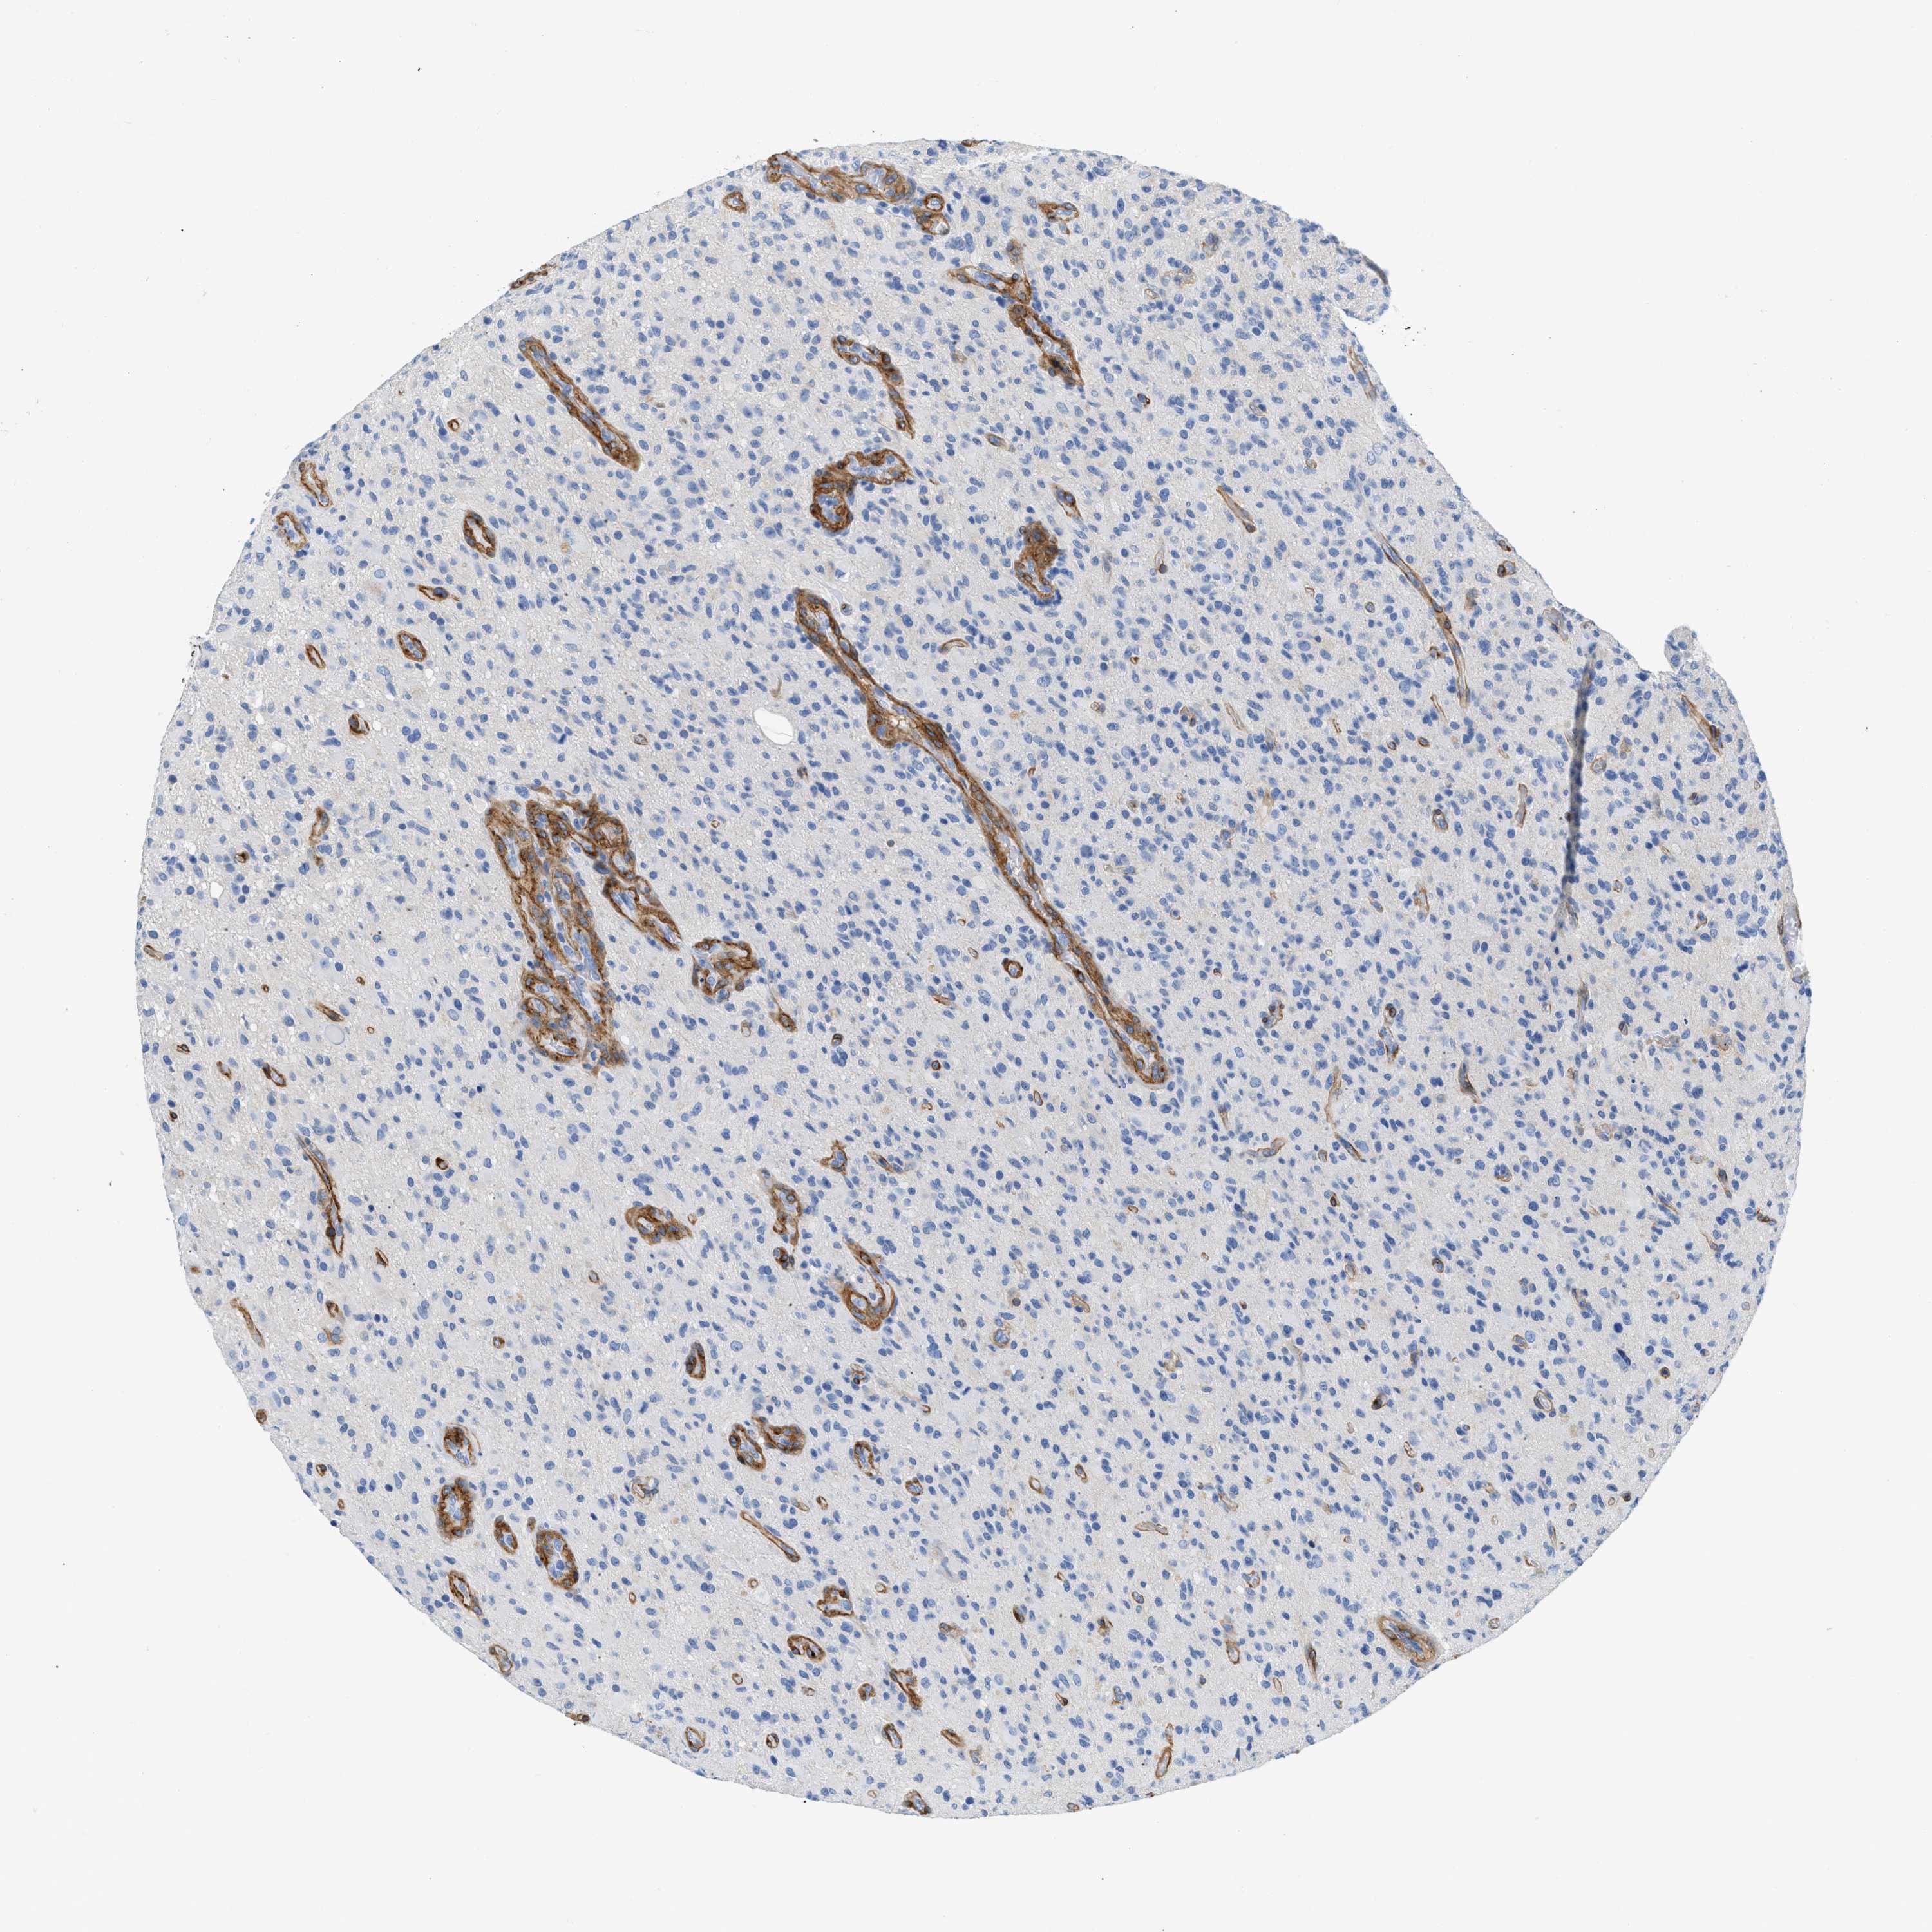

GLIOMA - Protein expressioni

A mouse-over function shows sample information and annotation data. Click on an image to view it in a full screen mode. Samples can be filtered based on level of antibody staining by selecting one or several of the following categories: high, medium, low and not detected. The assay and annotation is described here.

Note that samples used for immunohistochemistry by the Human Protein Atlas do not correspond to samples in the TCGA dataset.

Antibody stainingi

Antibody staining in the annotated cell types in the current human tissue is reported as not detected, low, medium, or high, based on conventional immunohistochemistry profiling in selected tissues. This score is based on the combination of the staining intensity and fraction of stained cells.

Each image is clickable and will lead to virtual microscopy that enables deeper exploration of all samples and also displays staining intensity scores, fraction scores and subcellular localization as well as patient and tissue information for each sample.

Antibody CAB003842

Antibody CAB018144

Staining

High

Medium

Low

Not detected

Intensity

Strong

Moderate

Weak

Negative

Quantity

>75%

75%-25%

<25%

None

Location

Nuclear

Cytoplasmic/membranous

Cytoplasmic/membranous,nuclear

Glioma, malignant, High grade

Glioma, malignant, NOS

Glioma, malignant, Low grade